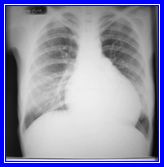

Femenino de 27 años de edad, sin antecedentes heredo

familiares de importancia. Tabaquismo positivo desde los 20

años con un índice tabáquico de 3 paquetes/año.

Tiene diagnóstico de esclerodermia desde hace 5 años,

tratada a base de prednisona. Inicia su vida laboral a los

18 años de edad como ayudante general en una empresa

de aparatos electrónicos (armado de teléfonos);

desde su ingreso ha estado en el área de soldadura

de circuitos. Refiere iniciar su padecimiento con fiebre,

malestar general y disnea progresiva a los medianos esfuerzos.

A la exploración física: femenina de edad aparente

mayor a la cronológica, inexpresiva, arcos de movilidad

en manos limitada a expensas de acartonamiento de piel, tórax,

rectilíneo, con presencia de estertores crepitantes

bilaterales bibasales.

Observe cuidadosamente la placa y sugiera de acuerdo al caso

descrito:

a) Fibrosis pulmonar difusa (E.S.P)

b) Neumonía

c) Bronquitis crónica

d) Pericarditis

e) Bronquiolitis obliterante